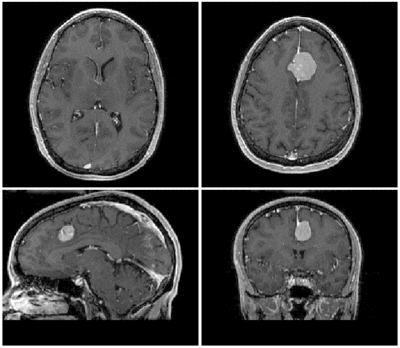

Slicer Registration Use Case Exampe #2: Inter-subject Brain MRI: axial T1 Tumor Growth Assessment

This is a classic case of change assessment. We want to know if the tumor changed since last exam.

MRI, brain, head, intra-subject, T1, tumor growth, meningioma, change assessment

reference/fixed : T1 SPGR , 0.9375 x 0.9375 x 1.4 mm voxel size, axial, RAS orientation.

moving: T1 SPGR , 0.9375 x 0.9375 x 1.2 mm voxel size, sagittal, RAS orientation.- Content preview: Have a quick look before downloading: Does your data look like this? Media:RegUC2_lightbox.png